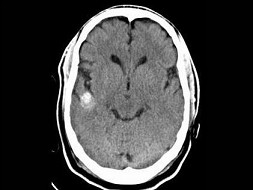

男,54岁,癫痫发作,结合图像,最可能的诊断是()

A.脑脓肿

B.脑出血

C.海绵状血管瘤

D.胶样囊肿

E.脑转移瘤